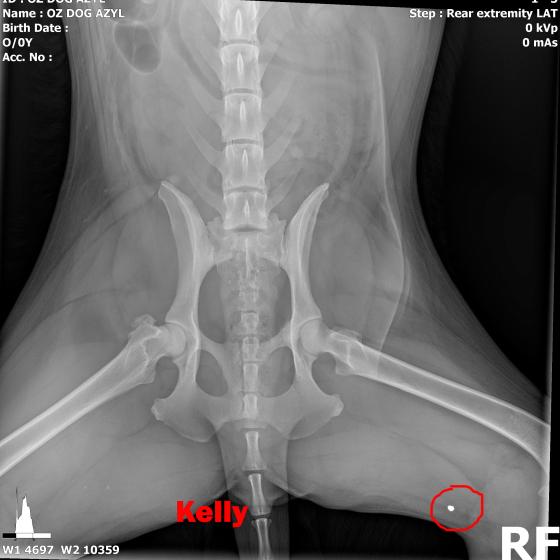

Image removed.KELLY - Vzali sme ju v rámci záchrannej akcie ČSKP z ranča, kde boli zvieratá v hororových podmienkach. Jedli, čo si našli, nekontrolovane sa medzi sebou množili a vôbec nie je vylúčené, že aj na ostatných si nejaký zlomyslený človek skúšal streľbu do diaľky. Kelly je úžasná, pokorná, mierumilovná, oddaná fenka, ktorá sa tak strašne zmierila s utrpením a svojim životom, že celé dni len tíško preleží v peliešku a občas si poplačká. Užíva si každé pohladenie, ale nechce byť nenásytná lebo nevie, či sa jej aj zajtra ujde. Ťažko je ju pohladiť bez toho aby Vám pri nej slza nevytiekla. Nevieme a nechceme si ani len predstaviť akým peklom si musela už prejsť. Kelly má diagnóz hneď niekoľko. Jej primárnym problémom je hrozné krívanie, doslova hopká ako zajko. Neudrží sa na zadných nohách. Môže to spôsobovať hneď niekoľko faktov.

V ľavej packe, medzi druhým a tretím prstom mala brok (treba si to predstaviť, ako keď máte kamienok v topánke a nech stúpate akokoľvek, vždy Vás tlačí. Lenže to je len kamienok a nie cudzí predmet v živom tkanive. Tú bolesť si radšej ani nepredstavujte.) V tej istej nožičke, v oblasti zadnej strany kolena bol ďalší brok, ktorý jej tiež prekážal pri narovnaní nohy. Prvým krokom bolo odstránenie týchto dvoch brokov, ktoré pravdepodobne spôsobovali najväčšie ťažkosti. Operácia sa konala 10.5.2020, dopadla výborne, Kelly sa zotavuje.

Píšeme ale "pravdepodobne" preto, lebo Kelly má tiež problém s krížovým väzom v kolene, ktorý má známky deformácie a má tiež hypointenzitu disku (to znamená, že má na platničke medzi stavcami pruh, ktorý vyčnieva a tlačí na miechu). Veríme, že vsetci strážni anjeli pri nej budú stáť a zvládne sa zotaviť, aby si mohla užívať taký život, aký mala žiť od narodenia. My sme pri nej, zabezpečíme jej všetko potrebné! Za diagnostiku, MRI a chirurgiu máme dve faktúrky, v celkovej výške 762,05€.